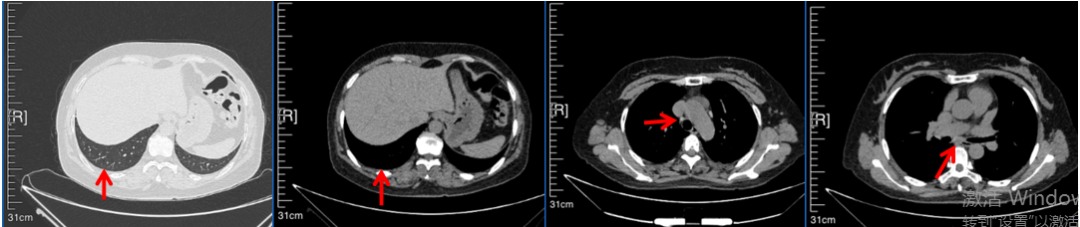

56岁,女性,无吸烟史饮酒史,既往体健。2023年02月患者体检发现肺占位性病变,胸部增强CT:右肺下叶后基底段结节;右侧锁骨上及纵隔内多发淋巴结肿大。PET-CT:右肺下叶周围型肺癌可能性大;1R、2L、3P、4R、4L及7组淋巴结转移可能性大。2023年02月就诊于本院胸外科行超声胃镜下纵隔肿物穿刺活检术,病理:结合免疫组化,符合肺腺癌。行NGS基因检测:EML4:exon20-ALK:exon20融合。PD-L1(克隆号22C3)TPS=55%。

2023年2月20日基线检查

2024年6月复查PR(最佳疗效)

2024年12月复查维持PR

2025年3月复查维持PR